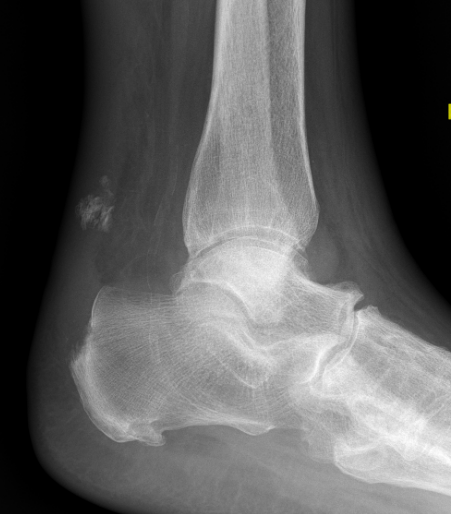

Xray

Exclude bony avulsion / insertional rupture